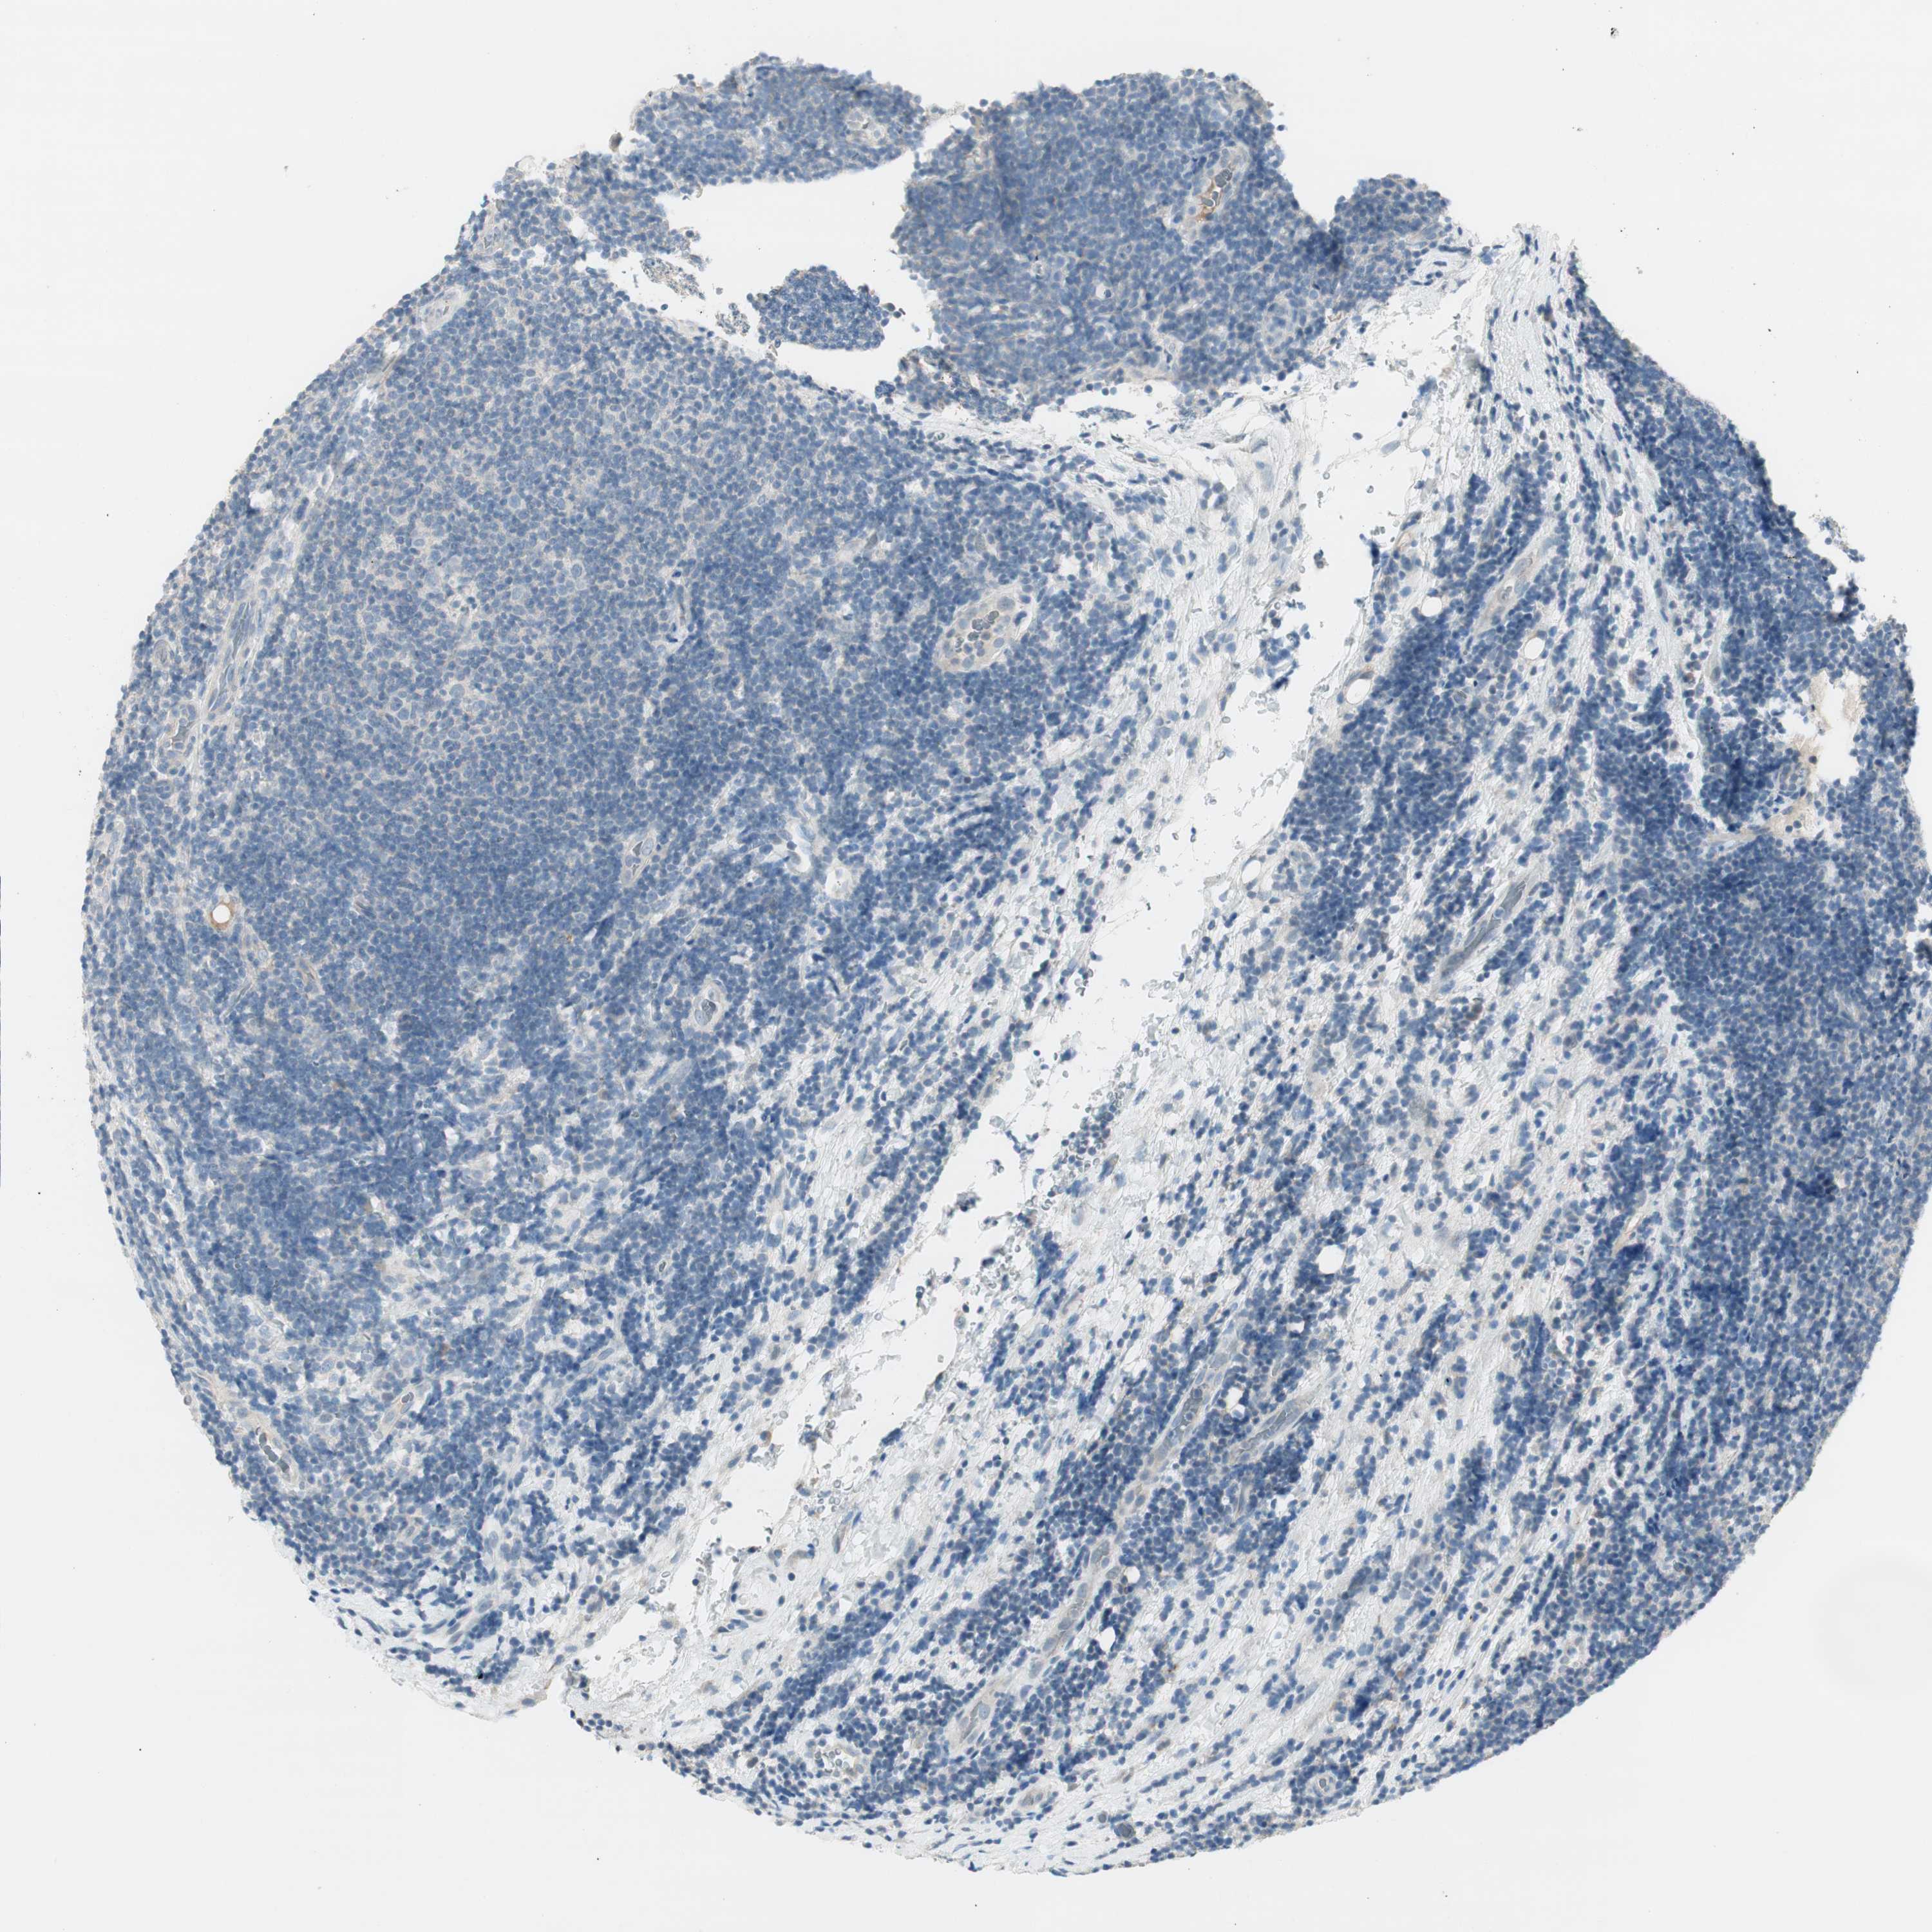

CANCER LYMPHOMA Show tissue menu

LYMPHOMA - Protein expressioni

A mouse-over function shows sample information and annotation data. Click on an image to view it in a full screen mode. Samples can be filtered based on level of antibody staining by selecting one or several of the following categories: high, medium, low and not detected. The assay and annotation is described here.

Each image is clickable and will lead to virtual microscopy that enables deeper exploration of all samples and also displays staining intensity scores, fraction scores and subcellular localization as well as patient and tissue information for each sample.

Antibody HPA008055

Staining

High

Medium

Low

Not detected

Intensity

Strong

Moderate

Weak

Negative

Quantity

>75%

75%-25%

<25%

None

Location

Nuclear

Cytoplasmic/membranous

Cytoplasmic/membranous,nuclear

Hodgkin's disease, NOS

Malignant lymphoma, non-Hodgkin's type, Low grade

Malignant lymphoma, non-Hodgkin's type, High grade